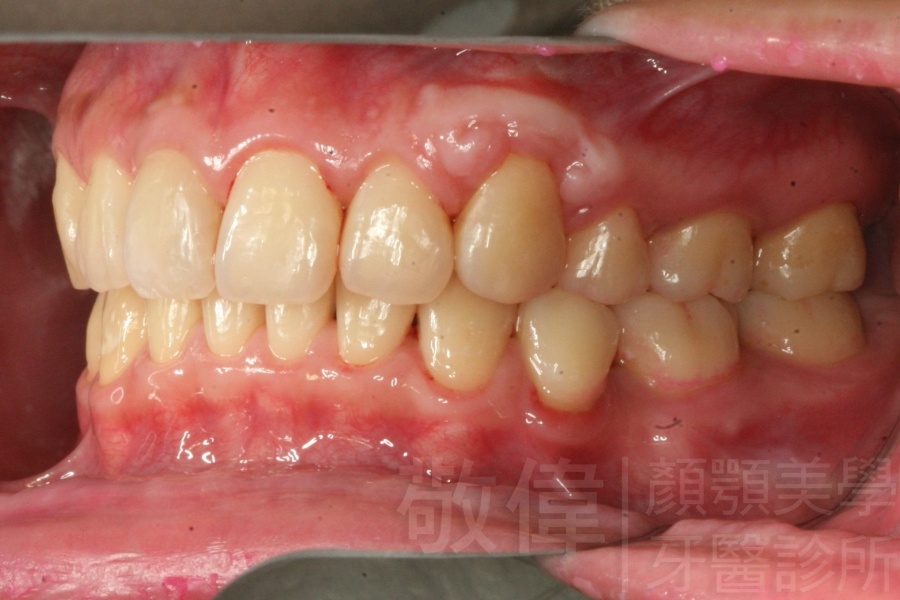

齒顏矯正/上顎暴牙且牙齒極度混亂

矯正前-右   矯正前-正   矯正前-左

矯正後-右   矯正後-正   矯正後-左

<個案說明>

上顎暴牙且牙齒極度混亂,經由矯正之後,臉型大幅度改善,牙齒的排列更加的整齊健康。相較於之前眼神充滿精神,自信心展現無遺。